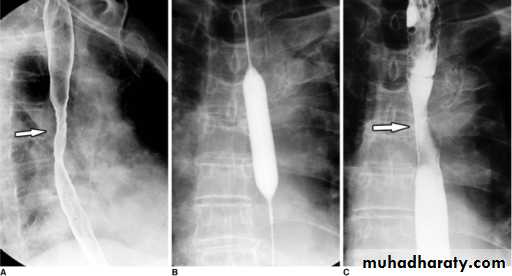

Dysphagia : Investigations

Dysphagia

Dysphagia is defined as difficulty in swallowing.It may coexist with heartburn or vomiting but should be distinguished

from both globus sensation (in which anxious people feel a lump in the throat without organic cause) and odynophagia (pain during swallowing, usually from gastro-esophageal reflux or candidiasis).

Dysphagia can occur due to problems in the oropharynx or esophagus.Oropharyngeal disorders affect the initiation of swallowing at the pharynx and upper esophageal sphincter.

The patient has difficulty initiating swallowing and complains of choking, nasal regurgitation or tracheal aspiration. Drooling, dysarthria, hoarseness and cranial nerve or other neurological signs may be present.

Esophageal dysphagia disorders cause dysphagia by obstructing the lumen or by affecting motility. Patients with esophageal disease complain of food ‘sticking’ after swallowing.